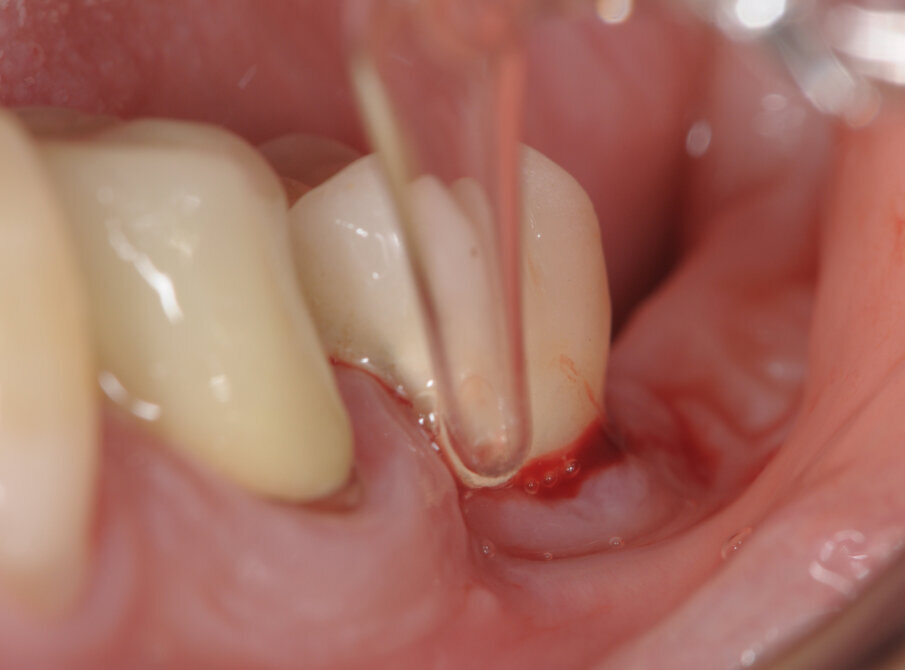

La paziente è stata trattata con protocollo Full mouth disinfection e nello specifico dell’impianto affetto da perimplantite in zona 36, è stata effettuata nella seduta operativa una strumentazione ultrasonica con inserto in PEEK per la rimozione del biofilm e delle concrezioni minerali. In seguito il sito è stato sottoposto a perio polishing con glicina e irrigazione della tasca perimplantare con H2O2. Successivamente è stata eseguita la prima applicazione di ozono.

La paziente viene sottoposta alla medesima seduta fatta nei primi 15 giorni con variazione nella frequenza portata ad 1 applicazione per settimana (Figg. 1-6).

A termine del trattamento descritto in precedenza da un punto di vista clinico abbiamo ottenuto un ripristino dei parametri di salute dell’impianto ovvero la scomparsa del sanguinamento dell’edema e della purulenza, in oltre si è verificata una riepitelizzazione dei tessuti molli limitrofi l’impianto. Da un punto di vista radiografico abbiamo ottenuto la neoformazione di osso attorno alle spire dell’impianto (con relativo aumento della stabilità) che a inizio terapia era da considerarsi potenzialmente come perso. La radiografia a 60 gg prima ed a 1 anno mostrano quanto prima descritto, ovvero un ripopolamento di componenti cellulari ossei sull’impianto con un recupero di 3 spire implantari (Figg. 7-9).